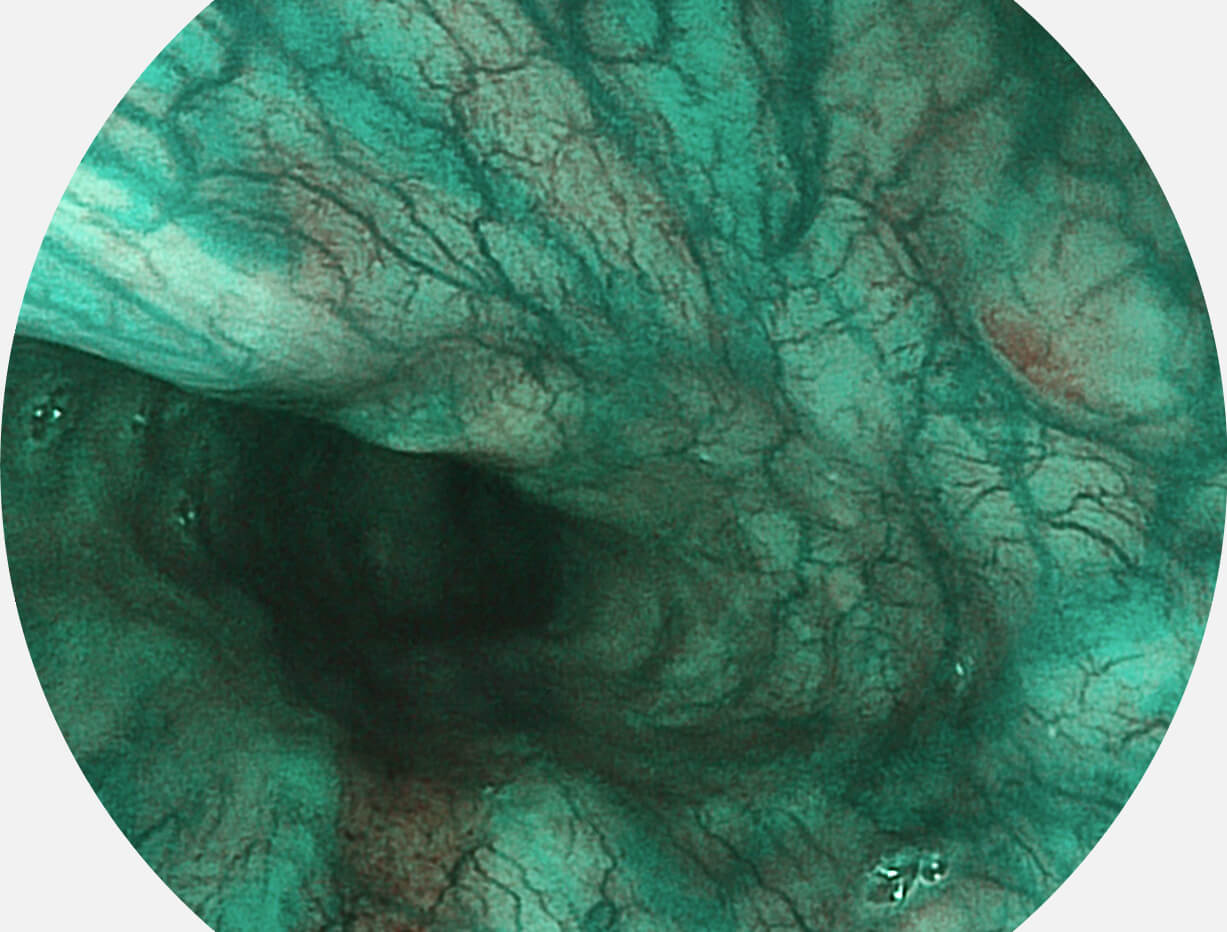

SFI图像

白光图像

Spectral Focused lmaging, SFI

图像具有高亮度、高黏膜血管颜色对比度的特点,且不改变粘液、食物残渣、粪便的基本颜色,可在中远景下进行观察,助力消化道早期疾病的诊断。

采用光路合束技术,光谱自由度高,实现了更丰富的照明模式,染色模式SFI及VIST,从远景到近景,助力消化道早期疾病诊断。